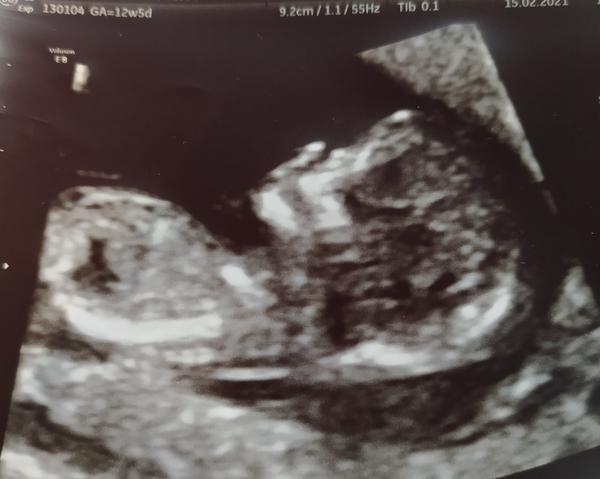

Ahoj holky, tak jak se máte? Já se dnes konečně dočkala screeningu a všechno je ve vzorném pořádku ❤️

@misak48 krásná fotka, gratuluji a ať se vám daří 🙂